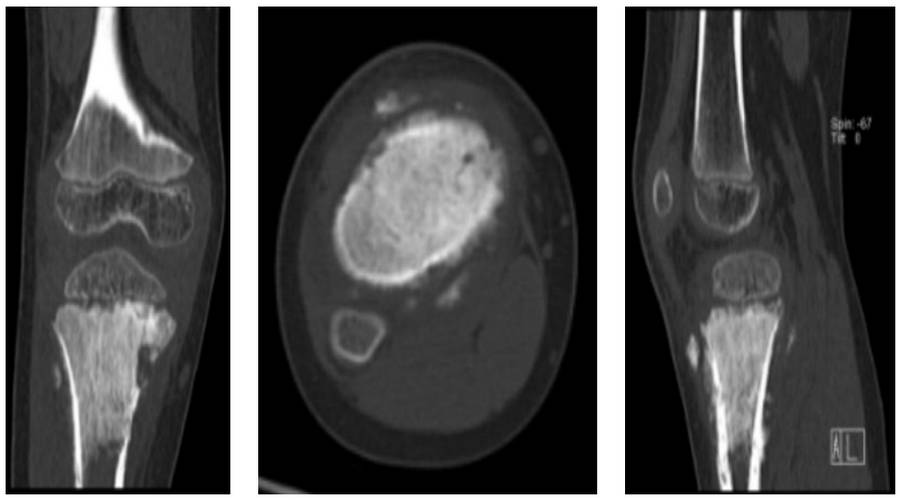

Ameliyat Öncesi: Tomografide aynı lokalizasyonda kemikte harabiyet ve yumuaşak dokuya uzanım görülmekte